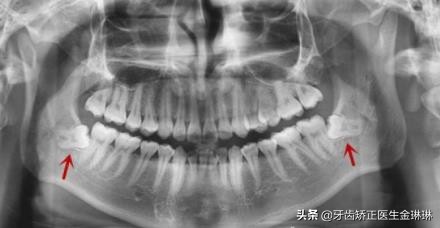

不过具体是否需要拔除,一般需要根据医生建议进行的,可能也有位置比较正的智齿是不需要拔除的,但是如果真的是位置正,就不会出现炎症,也不会疼痛了,所以大部分智齿就诊的患者,通常都是需要拔除智齿的。